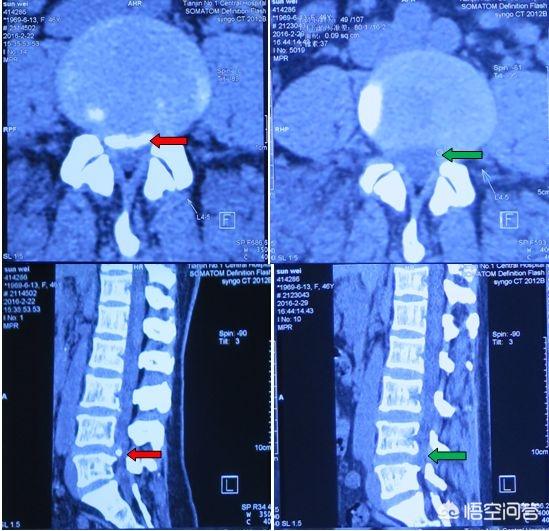

腰腿痛在做腰椎间盘CT检查的时候,往往有的人会发现有钙化,这个钙化可以是后纵韧带钙化,也可以是突出的髓核钙化,有的人钙化点压迫刺激到神经造成症状,相较于没钙化的处理要麻烦!

钙化,实际上是突出物较久或者长期腰痛,髓核脱水变性,慢慢形成的,临床上,我问的时候,多数是超过3~5年之上的人才会出现这种钙化,也许没有症状,可是早就已经发生椎间盘突出。

的确不少人在突出物钙化之后,康复难度会增加,不过这未必和钙化本身有关系,多数的钙化不会发生在突出物和神经根接触的地方,即便有也可以保守处理看一下,钙化的同时也表示问题发生的很早,持续很久,难度大一点是正常的。